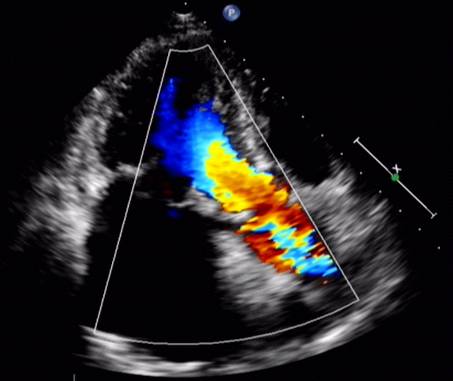

心超(2015-10-26)LA 4.6 (左右径×上下径:5.5×6.2)RA(左右径×上下径:3.7×5.0)RV2.2 LV 4.5 LVEF 0.47 TR 2.56(PG=26mmHg)心脏人工起搏器安装术后 二尖瓣人工生物瓣置换术后 双心房扩大 左室壁增厚 主动脉瓣钙化伴轻度关闭不全 三尖瓣轻度关闭不全 心功能降低 心包积液。

随访